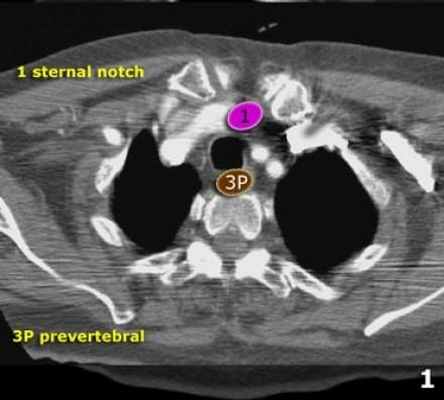

Надключичные лимфатические узлы

1 Нижние шейные, надключичные и лимфатические узлы вырезки грудины (левые и правые).

Располагаются по обе стороны от срединной линии трахеи в нижней трети шеи и надключичных областях, верхней границей является нижний край перстневидного хряща, нижней - ключицы и яремная вырезка рукоятки грудины .

1. Надключичные лимфатические узлы

В эту группу входят нижние шейные, надключичные и лимфатические узлы вырезки грудины.

Верхняя граница: нижний край перстневидного хряща.

Нижняя граница: ключицы и яремная вырезка рукоятки грудины.

Средняя линия трахее является границей между правой и левой группами.

1. лимфатические узлы вырезки грудины видны только на этом уровне и выше него